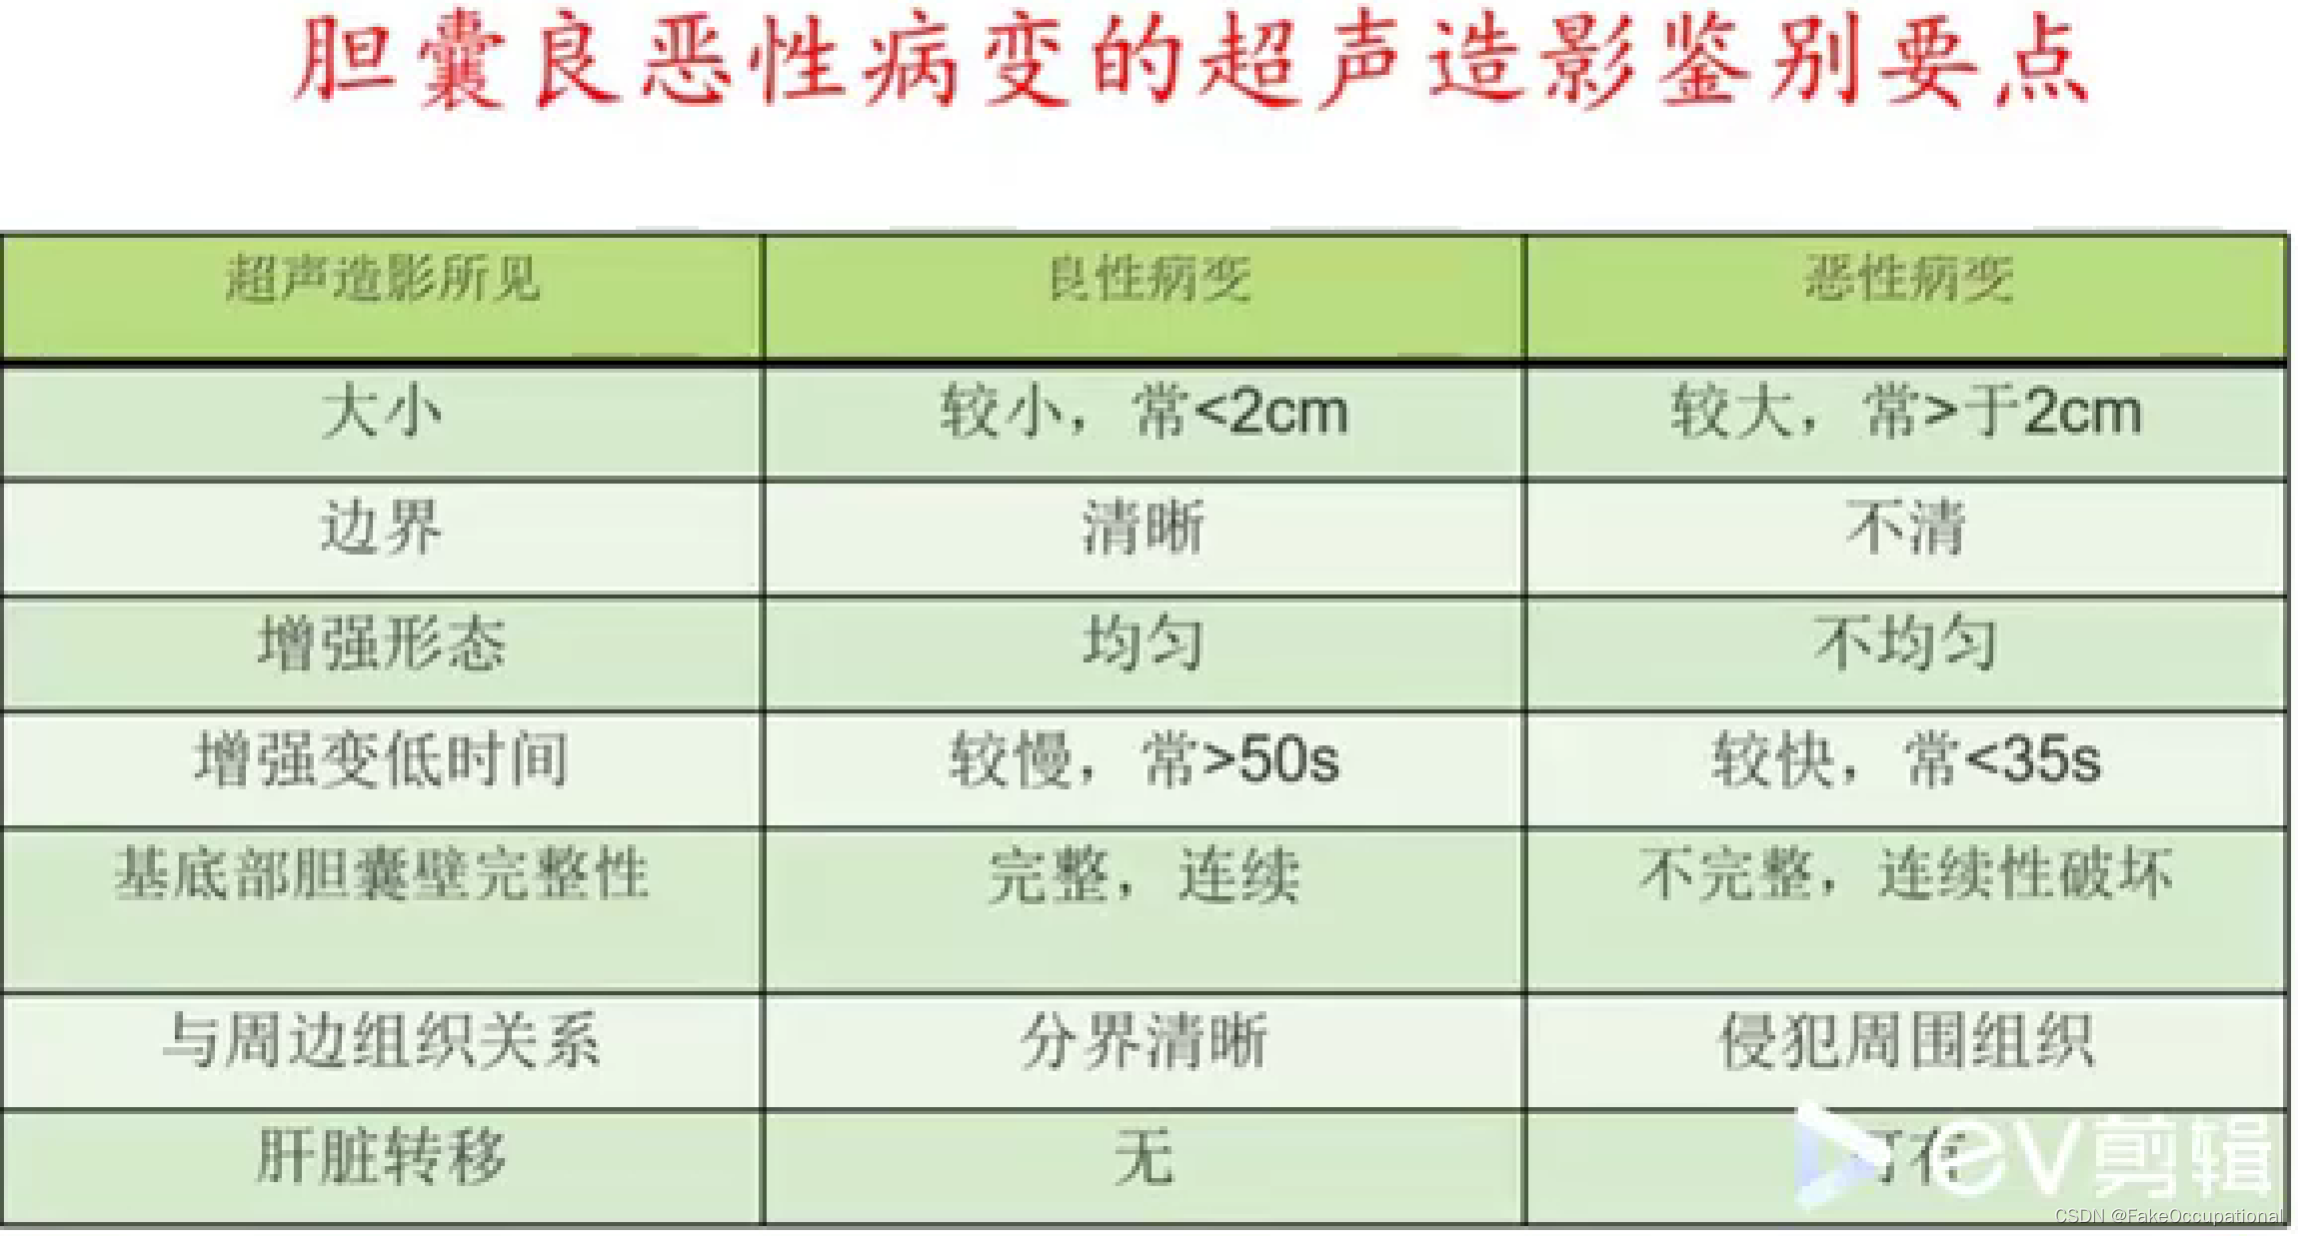

- 超声造影